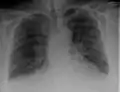

Chest X-ray

Chest X-rays are frequently used to aid in the diagnosis of CHF. In a person who is compensated, this may show cardiomegaly (visible enlargement of the heart), quantified as the cardiothoracic ratio (proportion of the heart size to the chest). In left ventricular failure, evidence may exist of vascular redistribution (upper lobe blood diversion or cephalization), Kerley lines, cuffing of the areas around the bronchi, and interstitial edema. Ultrasound of the lung may also be able to detect Kerley lines.[70]

Congestive heart failure with small bilateral effusions